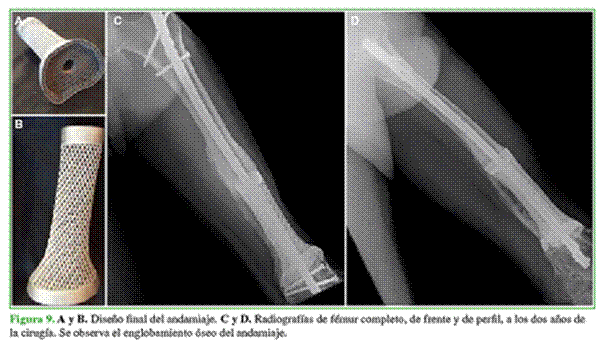

Desarrollo del implante

Se desarrolló un segmento intercalar en forma de cono truncado con mayor diámetro en ambos extremos para una mejor coaptación implante-hueso (Figura 9). Se optó por la estabilización con un clavo endomedular; por lo tanto, se diseñó un canal para alojarlo. Dada su longitud (13,5 cm), fue necesaria la colocación de un injerto, por lo que se decidió emplear una superficie rugosa para la incrustación de hueso esponjoso.

A los 150 días, se confirma la incorporación ósea completa mediante tomografía computarizada en todos los pacientes. Asimismo, en las radiografías simples, se observa el “englobamiento” óseo del implante, que se considera secundario a la cualidad inductora y la calcificación parcial de la membrana.